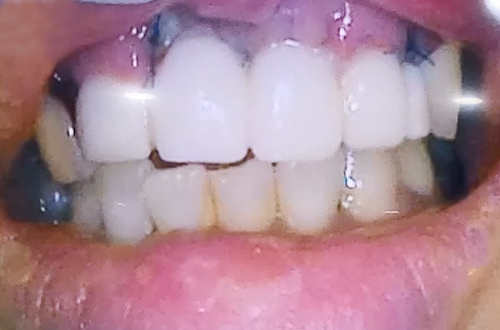

앞니 치아가 여러 개 빠진 상태의 임플란트 사례

AFTER

넘어지면서 앞니 치아가 여러 개 빠진 환자분이십니다.

첫번 째 앞니와 두 번째 앞니, 오른쪽 앞니가 빠진 상태로 방문하셨는데

오른쪽 두 번째 치아의 경우에도 많이 흔들리고 주변의 잇몸뼈들이

으스러져 있는 상태였기 때문에 두 번째 앞니까지 발치한 뒤

임플란트 2개로 치아 4개를 동시에 만들어 주는 치료를 계획하여 진행해드렸습니다.

당일 즉시 임플란트 수술을 진행하면서 뼈이식을 통해 단단하게 보강해 준 뒤

즉시 식립을 진행하고 임시치아를 만들어드리며 치료를 마무리하였습니다.